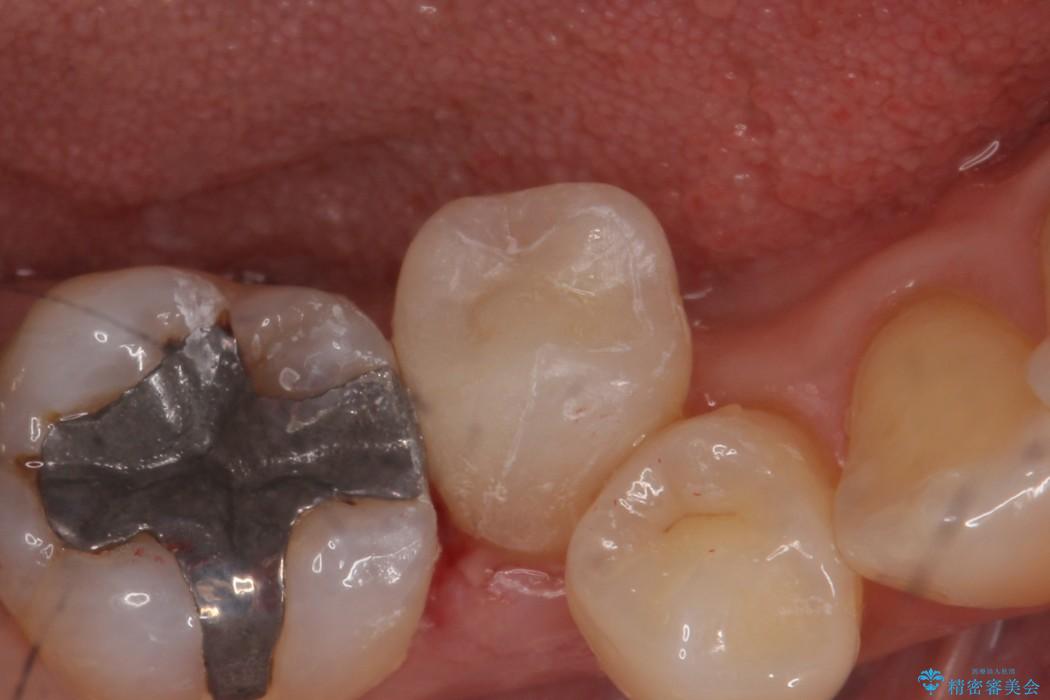

前の銀歯のように目立たず見た目のきれいな仕上がりとなり、大変喜んでいただきました。

保険診療と比べて自費診療では型どりの精度が良く、また周りの歯と馴染む色を選択することができます。

今回のケースでは下顎の歯が対象でしたが、人の目に触れやすい部分ではより患者様と話し合い、見た目にご満足いただけるような仕上がりを追及しております。